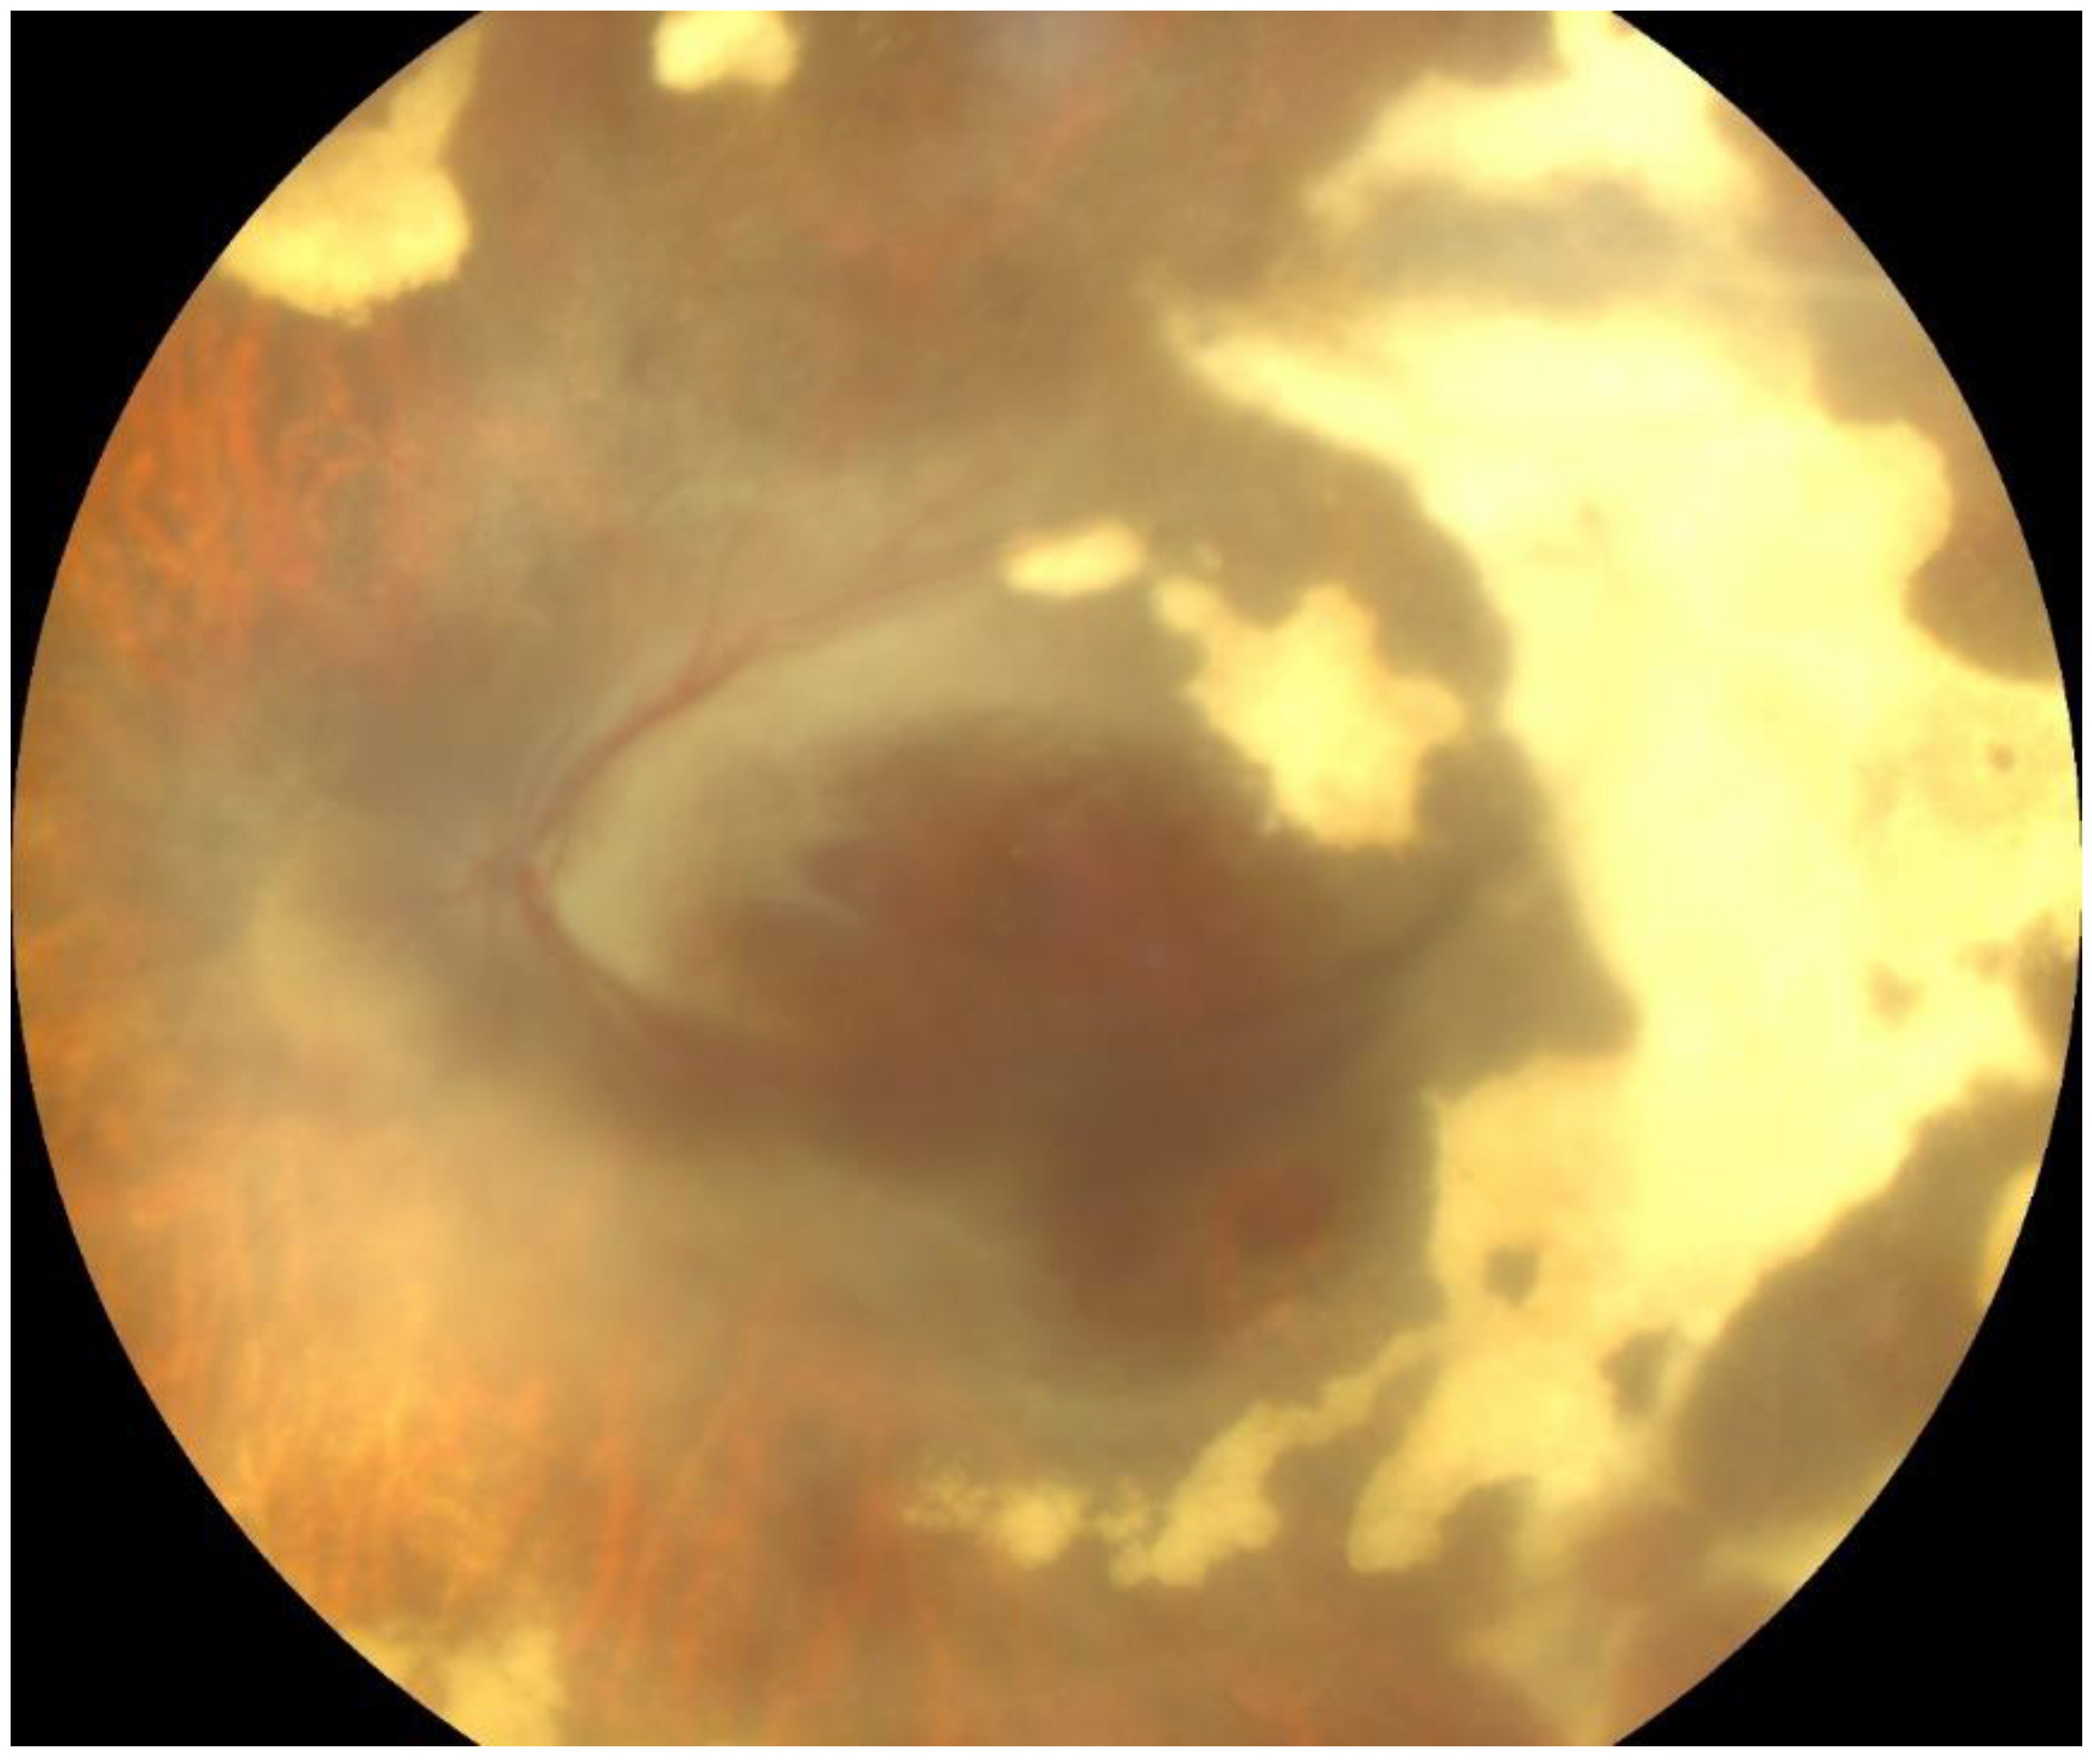

CMV retinitis is considered a stage 4 condition according to the World Health Organization (WHO) staging for AIDS, and can represent clinical failure as well as immunological failure. Induction phase of CMV retinitis was started with tablet valganciclovir 900 mg two times a day (BID) for one month, along with twice weekly monitoring of complete blood count, serum electrolytes, and renal function test. The anterior chamber inflammation was treated using topical mydriatic-agents, hypotensors, and corticosteroids during this stage. Given the mild nature of the COVID-19 infection (Figure 2), no specific antiviral treatment for SARS-CoV-2 was administered, and the focus remained on managing the CMV-related complications. A follow-up SARS-CoV-2 test was performed two weeks later, which remained positive, indicating persistent viral presence. However, by the fourth week, a subsequent RT-PCR test returned negative, confirming that the patient had cleared the SARS-CoV-2 infection after approximately four weeks.

Figure 2.

CT scan of the chest showing axial cross-sectional images of the lungs with multiple areas marked in orange circles. These marked areas represent ground-glass opacities. The opacities are distributed in both lungs and subpleural zones, suggesting a diffuse, bilateral pattern. The findings indicate a mild form of SARS-CoV-2 infection, with all lung lobes being affected.